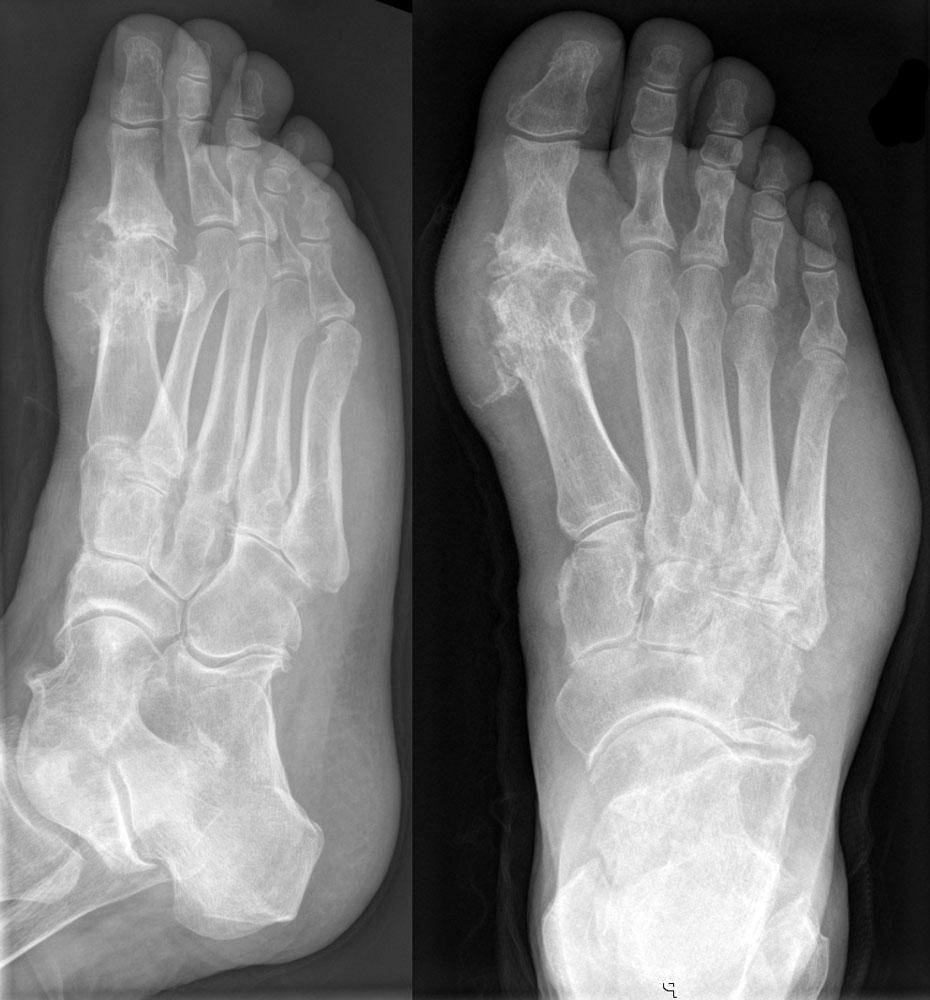

Определяющим критерием стадии артрита являются рентгенологические признаки. На начальных этапах развития какие-либо изменения отсутствуют. На второй стадии наблюдается разрушение гиалиновых хрящей, на третьей — подвывихи мелких суставов. Для артрита высокой степени тяжести (4 стадия) характерно полное или частичное сращение костных поверхностей.

В диагностике артрита наиболее информативны рентгенография, УЗИ, магнитно-резонансная и компьютерная томография.

Эти исследования позволяют выявить:

- разрушение хрящей;

- деформацию костных структур;

- локализацию и степень воспаления.